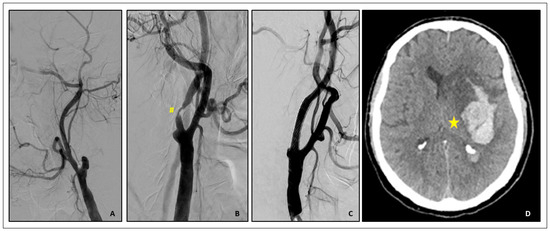

- (2)

- Rescue retrieval of a disconnected distal cerebral embolic protection device

- Brief Case description:

- (3)

- Plaque prolapse after carotid stenting

- Brief case description